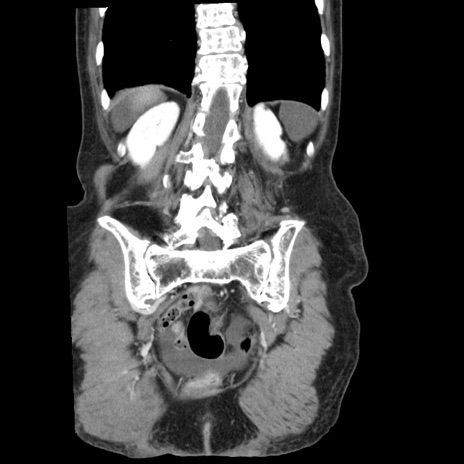

症例1(冠状断像)

【症例】80歳代女性

【主訴】腹痛

【現病歴】8時間前から腹痛あり来院。

【既往歴】糖尿病、脂質異常症、子宮体癌にて子宮全摘術

【身体所見】意識清明・会話良好だが腹痛で苦悶様、全腹部にわたって反跳痛と圧痛あり

【データ】WBC 13600、CRP 0.14、LDH 224、CK 90